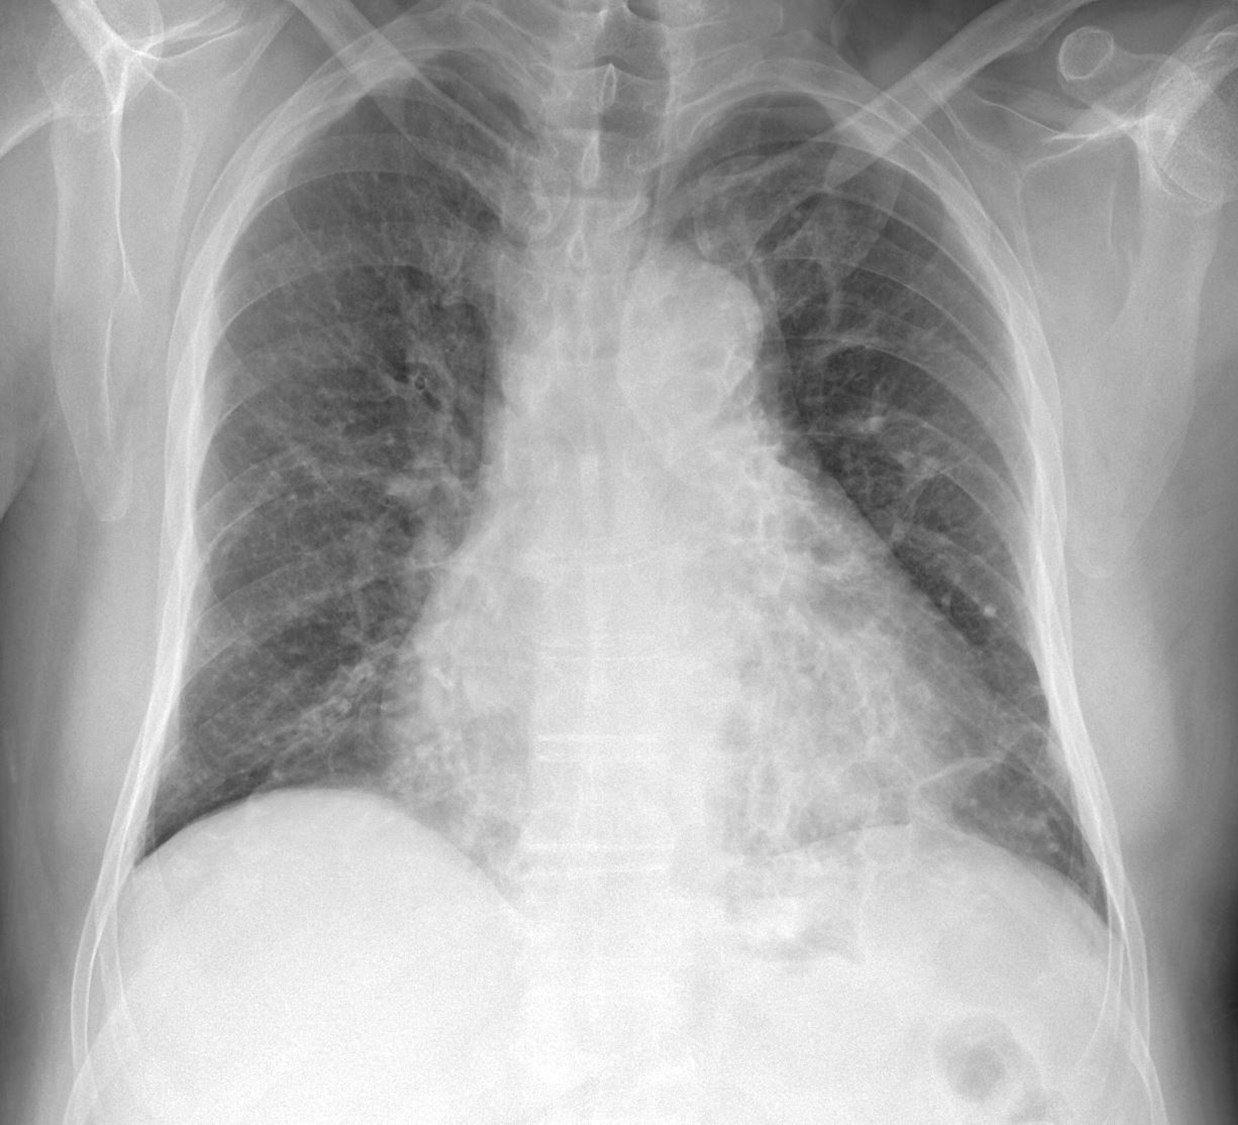

65세 여자가 6개월 전부터 간헐적으로 가래에 피가 조금씩 묻어나온다고 한다. 1달 전부터는 매일 찻숟가락정도 가래에 피가 묻어나온다고 한다. 비흡연자이고 특별히 복용하는 약은 없다고 한다. 어릴 적부터 감기에 자주 걸렸었다. 가슴 X-ray 사진은 아래와 같다. 청진상 우측 폐하부에 거품소리가 들린다. 진단은?

CXR: Bilateral multifocal patchy infiltrates, r/o ring shadows

• CXR상 여러 군데의 infiltrates가 관찰되나 폐렴 등이 저명하지는 않으며, ring shadow로 볼만한 병변들이 양쪽 폐하부에 확인된다.